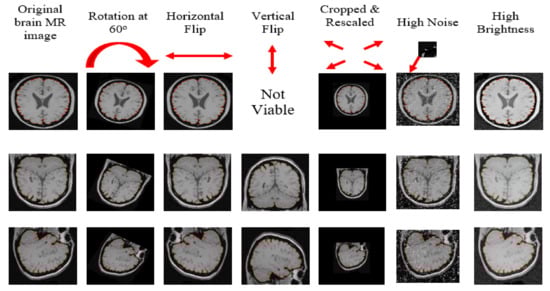

We divided brain MR images into three groups each for one stage of the experiment (training (75% = 1500 images), validation (15% = 300), and testing (10% = 200)) using the multistage random sampling technique elaborated previously, which ensured a fair proportion of all source-databases and anatomical orientations of the already selected 2000 images. Moreover, we augmented brain MR images by rotating, flipping, scaling, noising, and brightening, which offered a larger dataset with higher diversity to ensure the generalizability of Mask–RCNN. Such treatment also provided ground truth for the training of Mask RCNN to increase its capability for detecting objects with different orientations. The data augmentation of 1500 images provided 8122 augmented brain MR images as the system transformed each of the 878 axial images into 5 augmented images. Moreover, it transformed each of the 303 coronal images and 319 sagittal images into 6 augmented images. Figure 5 depicts the output of augmentation of brain MR images.

Figure 5. Augmentation of brain MR images reserved for training.